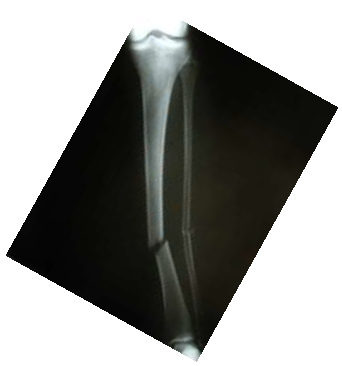

enunciado 323195-1

Assinale a alternativa que apresenta o diagnóstico da radiografia acima.